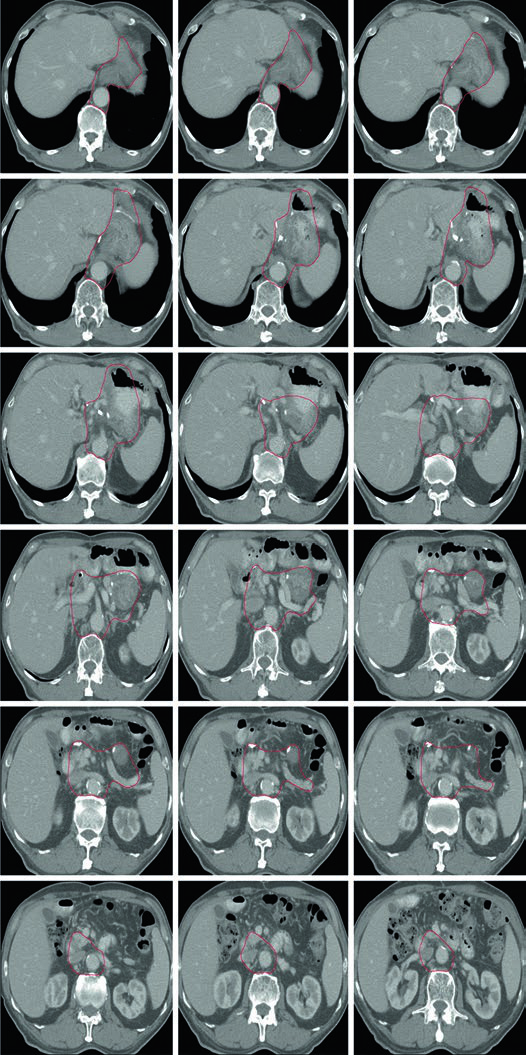

Caso 1: T1N1M0 Adenocarcinoma da Cárdia — Gastrectomia Total

Neste caso, o CTV engloba a anastomose esofagojejunal, o ligamento hepatogástrico, a artéria celíaca e o hilo esplênico. Como se trata de gastrectomia total em tumor da cárdia com linfonodo positivo, não há remanescente gástrico a incluir, mas os volumes nodais devem ser amplos.